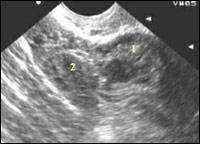

| Рисунок 4

| Эхокартина внематочной беременности Утолщенный фрагмент трубы с неоднородной внутренней эхоструктурой жидкость в малом тазу